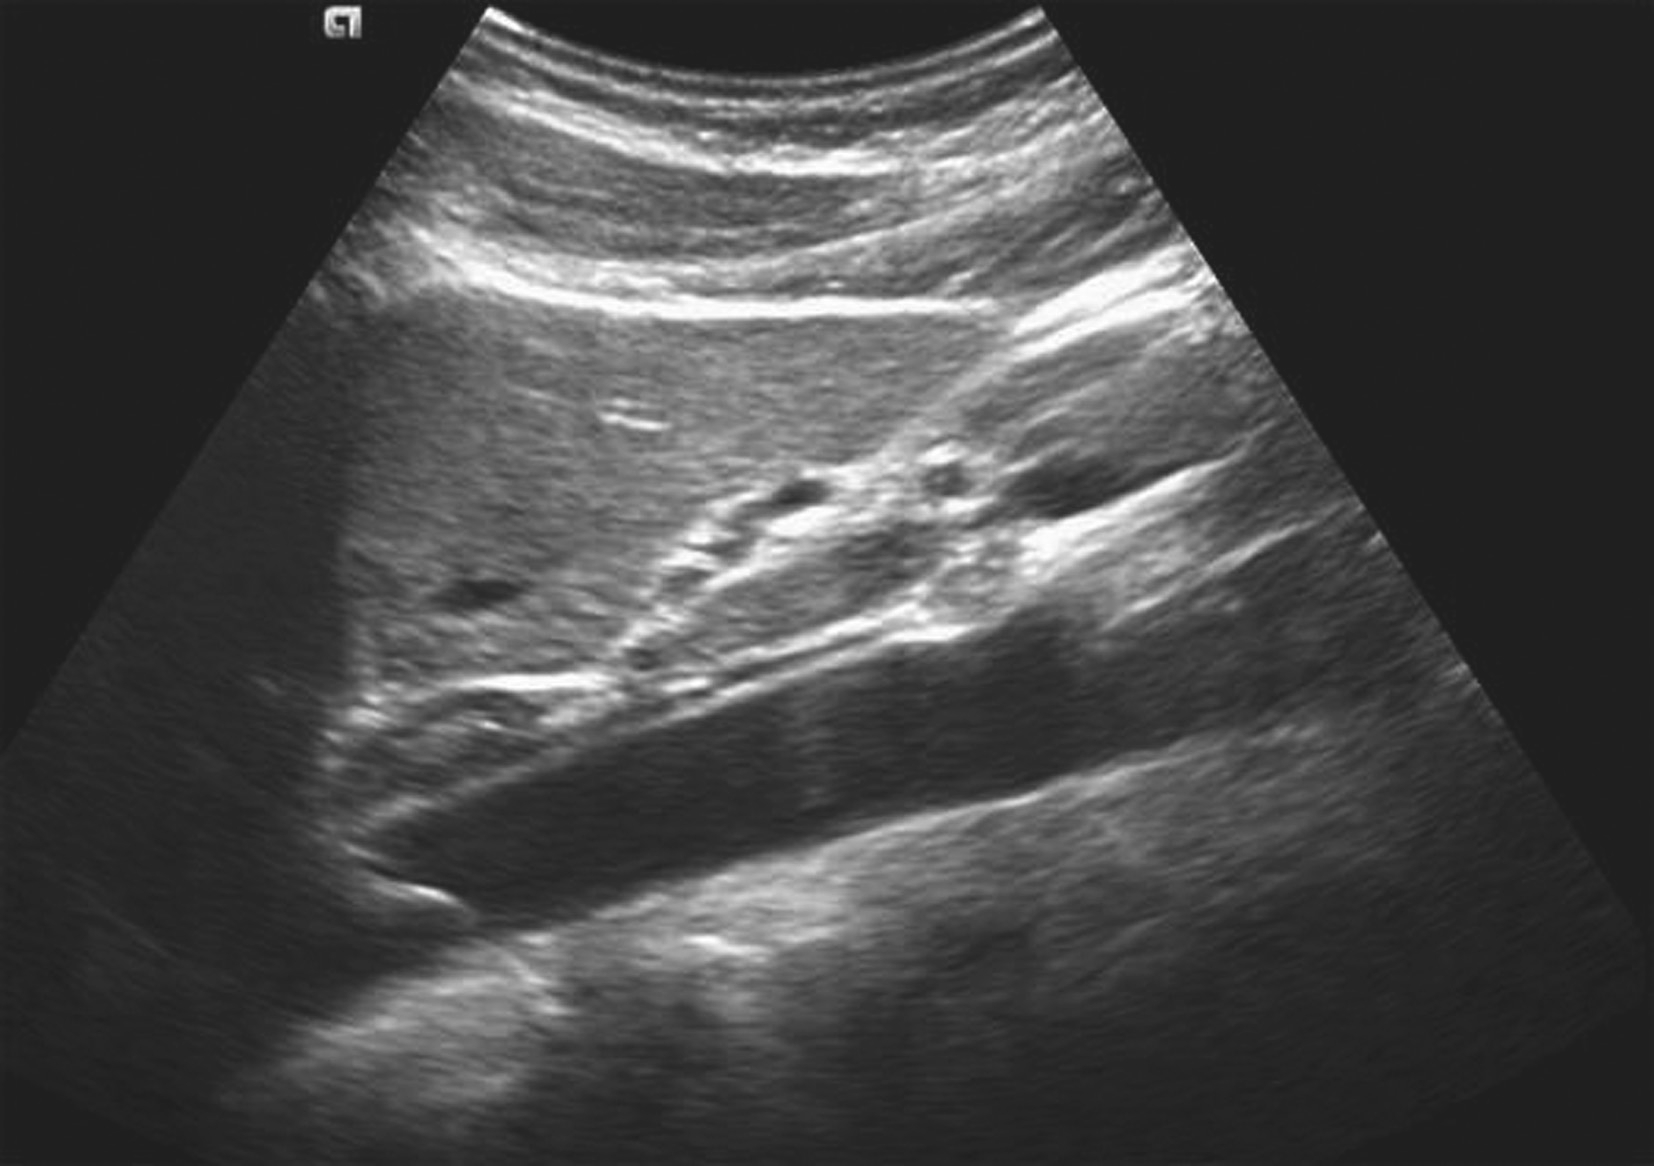

(1)灰阶超声:

肝门区结构紊乱,肝外门静脉周围或管腔内可见多条弯曲成团的血管,呈蜂窝状或网格状无回声区结构,在结构紊乱的肝门部仔细辨认可见管腔狭窄、壁增厚回声增强的门静脉管道,管腔内可见癌栓或血栓,部分可压迫胆道系统造成肝内外胆管扩张。可出现继发门静脉高压声像图改变,如脾肿大、脾静脉及肠系膜上静脉增宽,严重者可见腹水。

(2)彩色多普勒血流显像:

在肝门区蜂窝状或网格状无回声区结构内充满色彩暗淡的彩色血流信号;门静脉狭窄者于门静脉内探及少许连续性彩色血流通过,其周围蜂窝状液性无回声区呈红、蓝相间的不连续彩色血流信号;完全闭塞或栓子充填的门静脉内则无彩色血流信号显示;如图5-21-26所示。

(3)频谱多普勒表现:

门静脉海绵样变性区域于蜂窝状或迂曲的管状无回声区内均可探及门静脉样连续状低速血流频谱;如图5-21-27所示。

图5-21-26 门静脉海绵样变性二维灰阶图像

图5-21-27 门静脉海绵样变性彩色多普勒图像